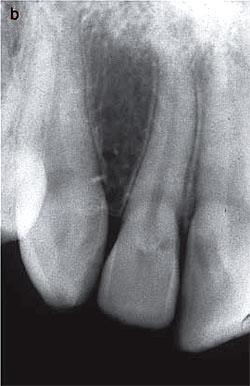

อันนี้คนละเคสนะครับ แสดงออก Class 2 คือ รอยโรคขนาดใหญ่ขึ้นจนฟันเริ่มมี pink discoloration

film ซี่ 11 lesion ซ้อนทับกับ pulp (อยู่ในแนว labio-lingual จึง superimpose กับ pulp แต่ยังไม่ expose pulp ครับ)

ความแปลกของ Invasive cervical resorption คือ มันไม่ค่อยจะ expose pulp ครับ จากรูปของอีกเคสนึง เป็น Class 2 จะเห็นว่า ถ้ารอยโรคอยู่ในตำแหน่ง proximal (ไม่ซ้อนทับ pulp) เราจะสังเกตเห็น radiopaque line บางๆ กั้นระหว่างรอยโรคกับ pulp (แสดงลักษณะของกลไกป้องกันตนเองของฟัน)

แม้ความคล้ายคลึงกับ caries จาก film ก็สามารถ diff diag ได้จากลักษณะของขอบรอยโรคที่ irregularity คล้ายๆ scallop pattern